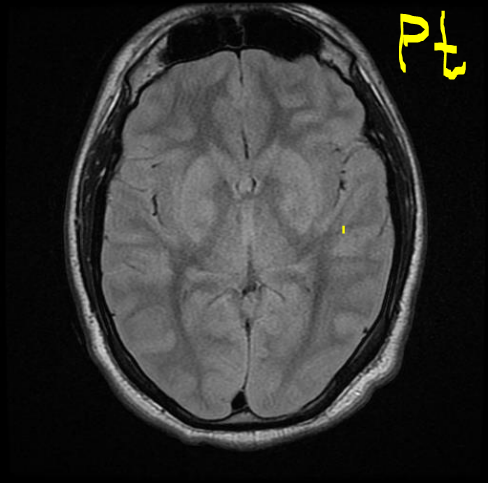

A 20 year old man tries to commit suicide by hanging himself. He is cut down after several minutes and is pulseless. He is resuscitated and regains a heartbeat and respiratory drive and cough to suctioning. Three days later, his exam has not changed. His MRI is attached.

What is the etiology of his brain injury?

Global hypoxia due to asphyxiation and compression of all four major vessels to the brain.

What areas or layers of the cerebrum are affected?

Lamina 3-5 of the entire cerebrum. These lamina are particularly sensitive to hypoxia and die earlier than other areas of the brain.

Why are the ventricles and sulci barely visible in the MRI?

The ventricles and sulci have been compressed by widespread cortical edema

When must this MRI have been taken? Why?

The MRI must have been taken a few days after the injury; cortical edema takes days to show up. Glial cells and astrocytes are able to survive longer (20-30min) during ischemia than neurons (6-10min); their (proportionately greater) survival kept most of the brain’s structure intact despite widespread neuronal death.